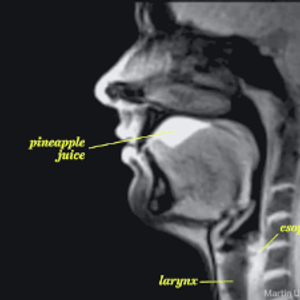

#爱你爱到骨头里#【MRI下诡异而奇妙的人体】这是一段用核磁共振成像技术制作的动态短片,将人类喝水、亲嘴、嘿咻、拉翔、生娃、说中文、说德文等日常活动展现得毫纤毕现、一览无遗。doge微猎奇,微暴,慎点。